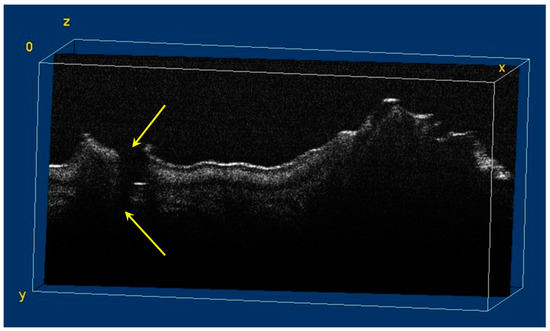

The image processing using ImageJ software showed the spatial disposition and extent of the hypomineralization lesions and hypoplasia (Figure 6, Figure 7, Figure 8 and Figure 9).

Figure 8.

Three-dimensional OCT reconstruction (in ImageJ) of a hypoplasia lesion (Axis 0Y). The yellow arrows indicate a continuous area characterized by the absence of signal, similar to the appearance of a dental crack or fracture.

Figure 9.

Volumetric reconstruction (in ImageJ) of a hypoplasia lesion. The yellow arrows indicate the affected area, defined by a discontinuity of the enamel at the surface of the tooth; this lesion extends beyond the dentinoenamel junction.